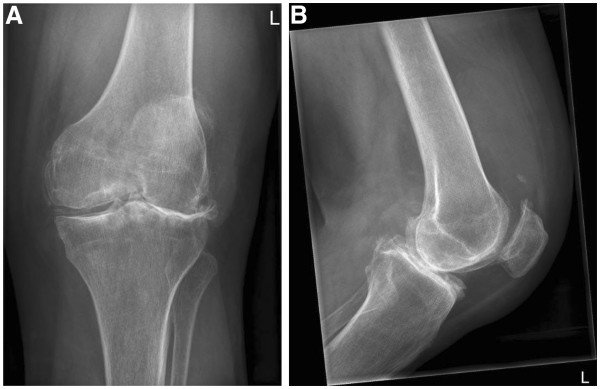

Osteoarthritis

Source: Radiopaedia

Osteoarthritis refers to degeneration of a joint due to repeated microtrauma. As the cumulative trauma outpaces the body’s ability to heal itself, radiographically appreciable changes occur. In the case above, there is a very large joint effusion, caused by the inflammatory response to insult as well as all four of the cardinal plain film radiographic signs of degenerative change (joint space narrowing, osteophytosis, articular sclerosis and subchondral cyst formation).

As a bonus, this patient also has chondrocalcinosis of their medial meniscus (often associated with but not necessarily indicative of OA; see CPPD).